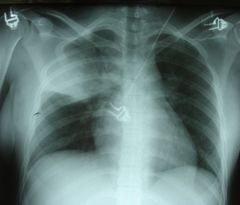

Elle fait savoir que la pneumonie constitue la forme la plus courante d’infection à pneumocoque grave et représente 18% de la mortalité infantile dans les pays en développement. ‘’C’est l’une des deux principales causes de mortalité chez les jeunes enfants.’’